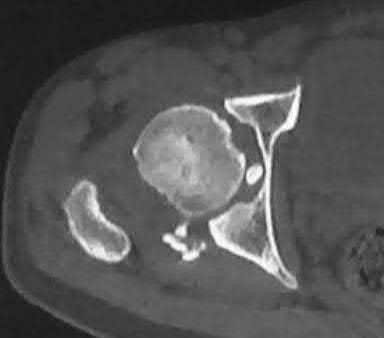

A 15-year-old boy presents with a permeative lytic lesion in the femoral diaphysis with aggressive periosteal reaction ('onion skinning'). Biopsy reveals uniform small round blue cells. Cytogenetic analysis of this tumor will most likely demonstrate which of the following translocations?

The clinical and radiographic description is classic for Ewing sarcoma. The characteristic cytogenetic abnormality is a balanced translocation t(11;22)(q24;q12), which fuses the EWS gene on chromosome 22 with the FLI1 gene on chromosome 11. This is seen in approximately 85-90% of Ewing sarcomas. t(9;22) is the Philadelphia chromosome (CML), t(X;18) is seen in synovial sarcoma, t(2;13) in alveolar rhabdomyosarcoma, and t(12;16) in myxoid liposarcoma.